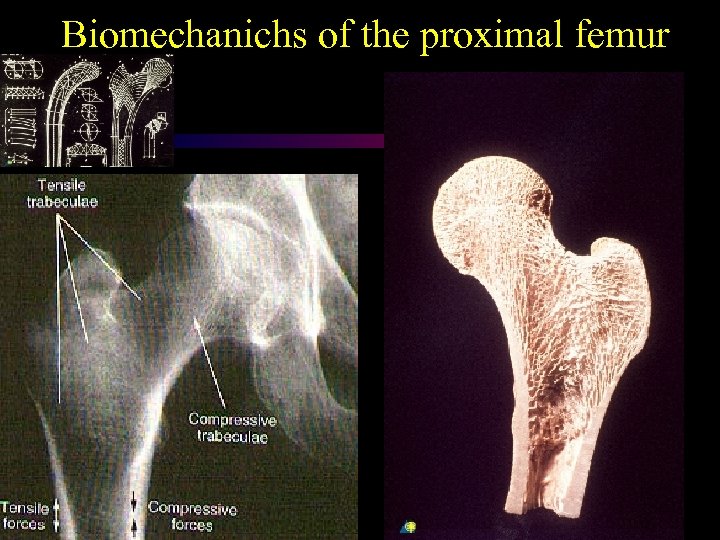

Biomechanichs of the proximal femur

Biomechanichs of the proximal femur

Biomechanichs of the proximal femur

Biomechanichs of the proximal femur

Biomechanichs of the proximal femur

Biomechanichs of the proximal femur